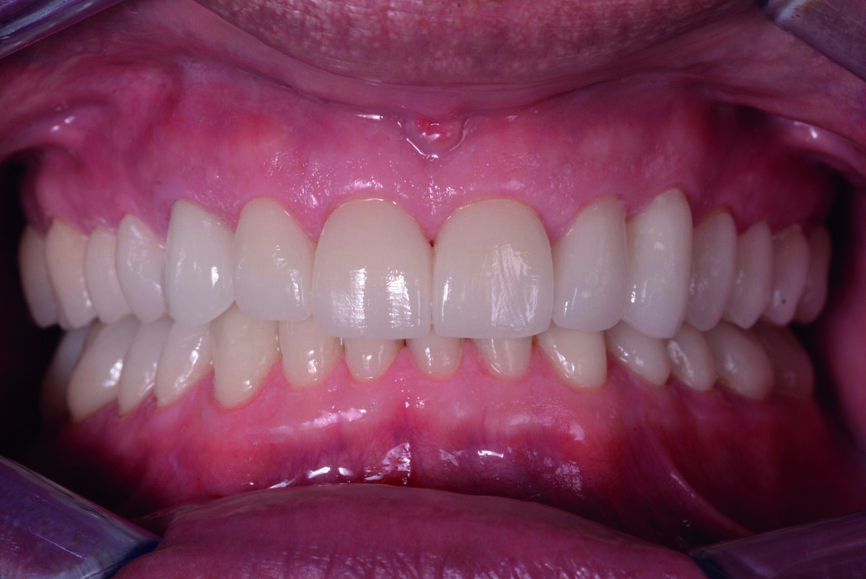

Figs. 13 et 14 : Photographies intraorales après le traitement.

Les couronnes (#11–13 et 21–23) et les facettes (#14–17, 24–27, 31–37 et 41–47) sont collées sur les dents piliers au moyen d’une colle composite photopolymérisable (Futurabond U et Bifix QM, VOCO). Un dispositif équipé d’une lampe LED à haute puissance (Celalux 3, VOCO) est utilisé pour la photopolymérisation (Figs. 11 et 12).

Après l’élimination de l’excès de colle composite, l’occlusion est adaptée et vérifiée à l’aide du système d’évaluation occlusale T-Scan (Tekscan). Une contention amovible en résine acrylique est utilisée pour protéger les restaurations définitives, et celles-ci sont vérifiées six mois plus tard. À ce moment, les restaurations sont toujours stables et ne présentent aucun signe de fracture (Figs. 13–15). Le patient déclare également qu’il n’a plu souffert de maux de tête grâce à cette nouvelle dimension verticale d’occlusion.